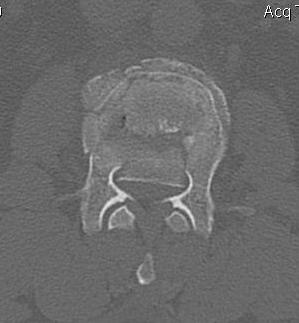

CT

Look for canal compromise

- cord signal change

- kyphotic deformity

Retropulsed fragments

- always between pedicles

- typically one or two main fragments (saloon door)

- assess canal compromise